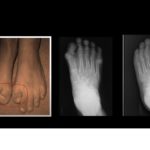

Fibrodysplasia Ossificans Progressiva